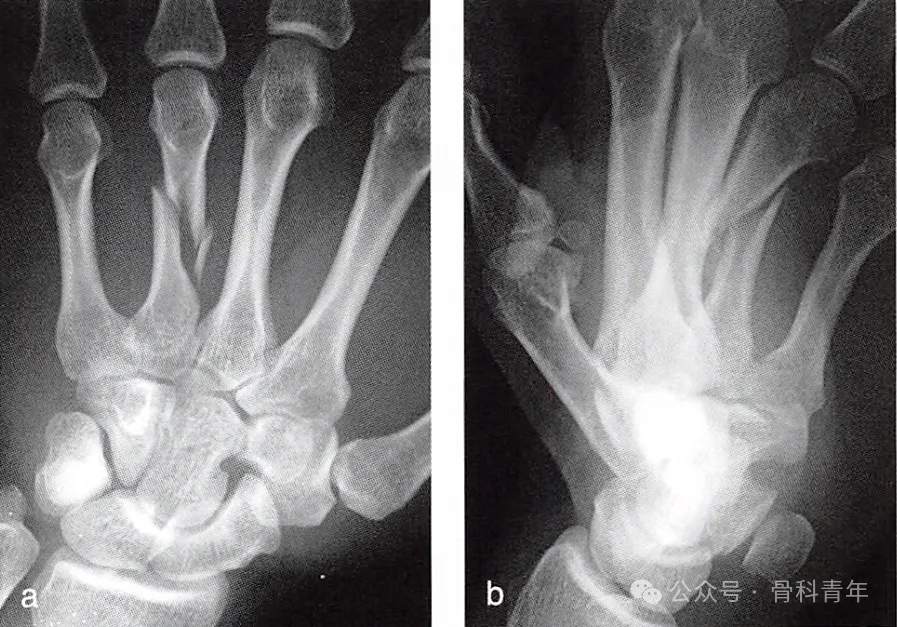

掌骨骨折占手部骨折的60%,直接暴力损伤可导致掌骨横行骨折,间接、扭转暴力常导致螺旋型或粉碎骨折。大部分掌骨骨折可采用闭合复位石膏固定,而对成角>30°、旋转>5°及短缩>5mm且闭合复位困难患者,建议手术治疗,避免手指功能障碍。第4掌骨骨折由于临近掌骨的遮挡,且掌侧软组织较为丰厚,闭合复位及维持复位更加困难,手术治疗较为常见。

近年来,闭合复位克氏针内固定具有的微创手术,无需二次手术的优势,使其在掌指骨骨折中应用愈发广泛。来自河北三院的学者,发表文章描述了一种第4掌骨骨折闭合复位克氏针内固定的方法,供大家参考: